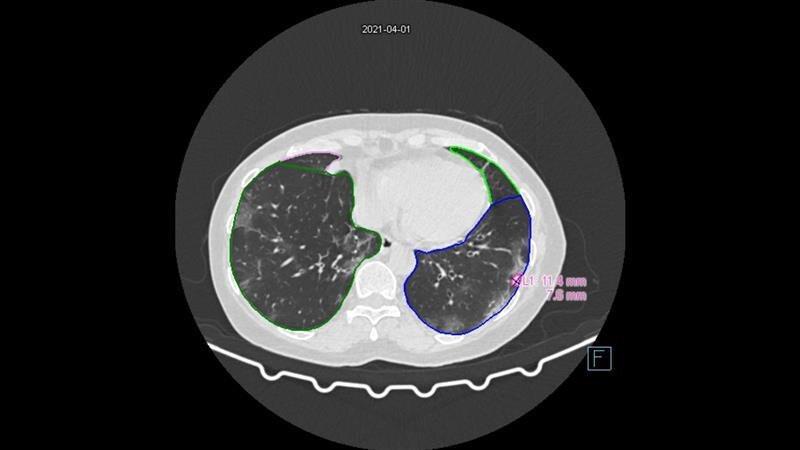

- Low Dose CT

- AI-based automated image analysis